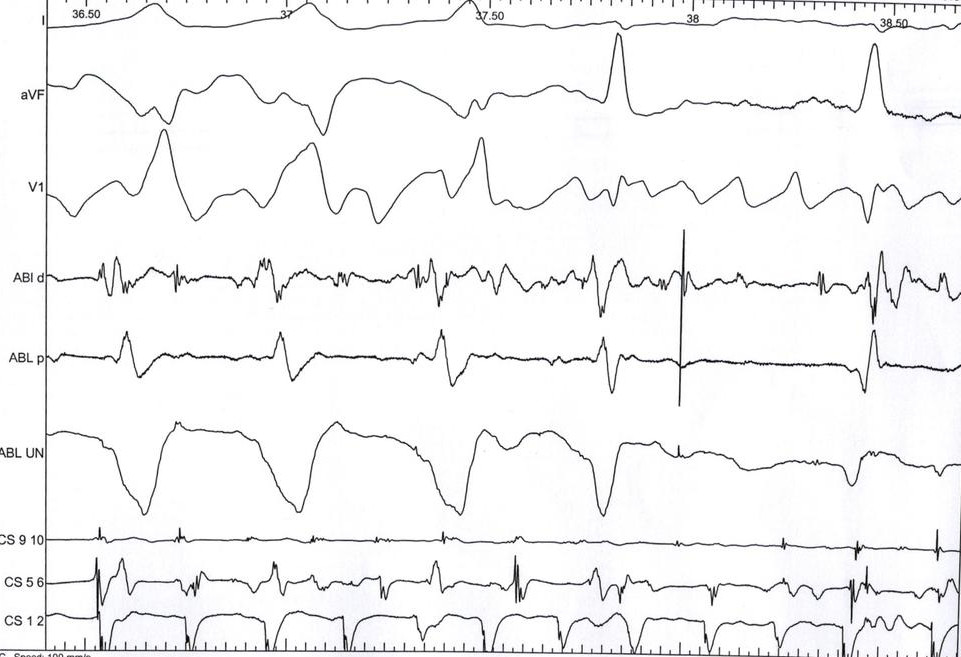

Dont clip ablation signals

abl_clipping1.jpg

abl_clipping2.jpg